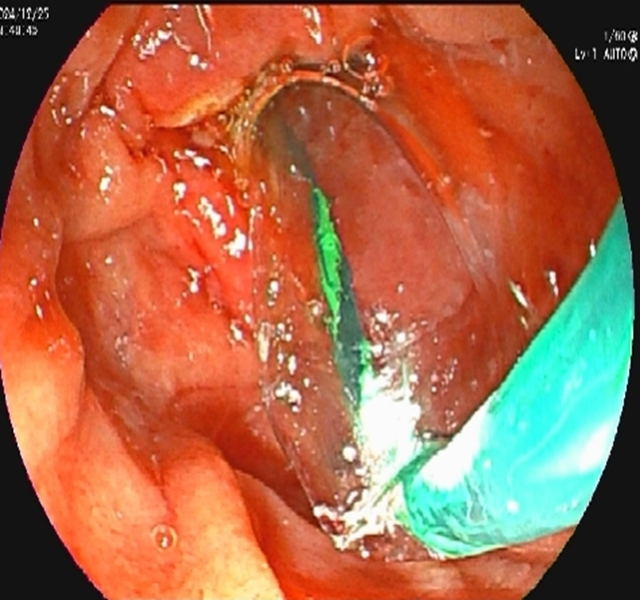

内镜到达十二指肠乳头时,切开乳头的瞬间,大量白色脓液喷涌而出(证实胆道高压、感染极重);随后用球囊扩张乳头(扩大开口),顺利取出嵌顿的结石。

内镜逆行胰胆管造影的关键操作是乳头切开引流+取石:医生用微型电刀切开狭窄的乳头(类似“扩大下水道口”),再用网篮或球囊取出结石。从切开到取石,通常仅需10-30分钟,能迅速降低胆道压力,让淤积的脓性胆汁通过切口及鼻胆管流出体外—这是控制感染、逆转休克的关键。